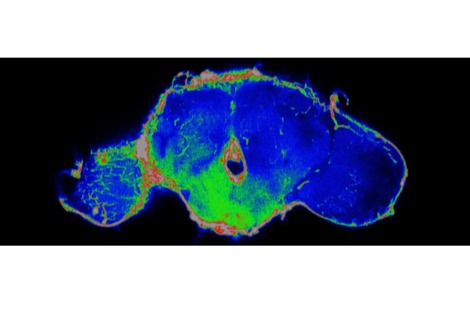

قام الباحثون برصد التغيرات في 76 مؤشرًا دمويًا، مثل مستويات البروتينات والدهون والأملاح، والتي تشير إلى وظائف الكبد والكلى والدم والعضلات والعظام والجهاز المناعي. ووجدوا أن كل مؤشر من هذه المؤشرات يختلف اختلافًا كبيرًا عن مستويات ما قبل الحمل أثناء الحمل، قبل أن يعود تدريجيًا إلى مستويات ما قبل الحمل أو يتجاوزها قبل أن يستقر عند مستوى ما قبل الحمل.

من الجدير بالذكر أن العلماء وجدوا أنه في حين أن 36 من هذه العلامات، بما في ذلك تلك المتعلقة بتخثر الدم، قد عادت إلى حالتها الطبيعية في غضون شهر بعد الولادة، فإن 31 علامة استغرقت أكثر من 10 أسابيع للتعافي. على سبيل المثال، استغرقت بعض التغيرات في الكبد والجهاز المناعي حوالي 5 أشهر للعودة إلى مستويات ما قبل الحمل، واستغرقت العديد من علامات الكلى ما يقرب من نصف عام. واستغرقت بعض علامات العظام والعضلات وقتًا أطول. يقول ألون إن ما يعنيه هذا بالضبط لصحة المرأة غير واضح، ولكن يجب استكشافه في الأبحاث المستقبلية.